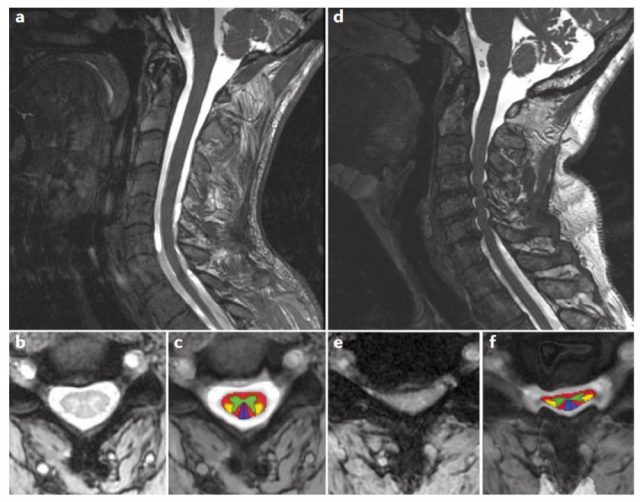

Εικόνα 2: Αριστερά, φυσιολογική μαγνητική τομογραφία (a-c) όπου φαίνεται ότι δεν υπάρχει πίεση επί του νωτιαίου μυελού και τα νευρικά δεμάτια (έγχρωμη εικόνα) δεν είναι συμπιεσμένα. Δεξιά, αυχενική μοίρα με εικόνα σπονδύλωσης και πίεση του νωτιαίου μυελού.